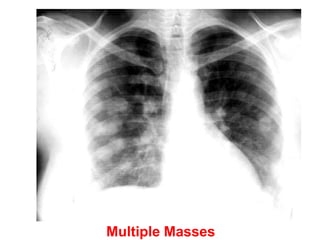

Multiple Masses

Multiple Nodules: Diagnosis? Metastases

68 154 slides Multiple Nodules:Diagnosis? Metastases 68